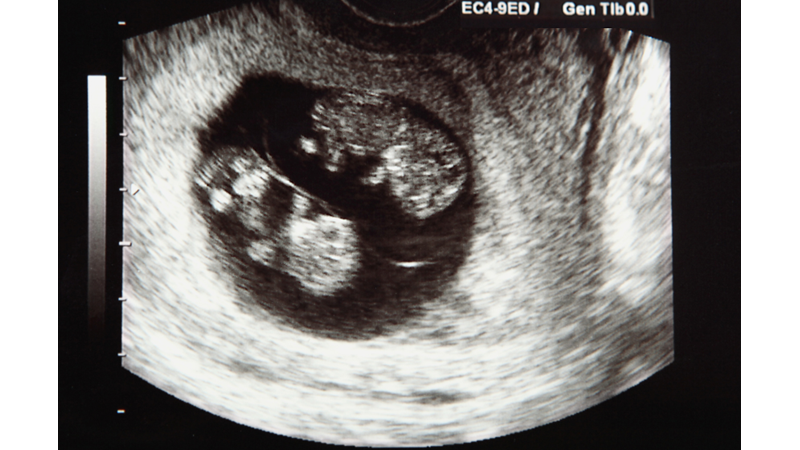

İngiltere'deki "Çoklu Doğum Vak­fı"nın başkam Dr. Elizabeth Bryan, eğer "1.80 boyunda, geç 30'lu yaşlar­da, beş çocuklu ve cinsel olarak aktif bir Nijeryalı"ysanız, karın kardeşi ikiz sahibi olma şansınızın çok yük­sek olduğunu, buna karşın, "1.50 bo­yunda, 20 yaşında, seks hayatı dü­zenli olmayan, ilk çocuğuna hamile ve ailesinde ikiz bulunmayan bir Ja­pon kadını"ysanız, karın kardeşi ikiz sahibi olma şansınızın bulunmadığını söylüyor. Nijerya'daki Yorubalar'da ikiz çocuk sahibi olma oranının yük­sekliğiyle Japonlar'ın ikiz çocuk sa­hibi olma şansının azlığının temelin­de etnik faktörler var ama, etnik fak­törlerdeki farkı saptamak da o kadar kolay değil.

İkiz doğurmayla, yu­murtaların olgunlaşmasını sağlayan "gonadotropin" hormonu arasında bir ilişki olduğu düşünülüyor. Yük­sek oranda gonadotropin, yaşı daha büyük olan kadınlarda ve Nijeryalı­lar'da görülüyor. Nijeryalılar'daki durumun, çok fazla yedikleri yerel­masından kaynaklandığı sanılıyor. İkizlerin varlığı esrarını korumaya devam ediyor ama, onlar, yüzyıllar­dır merak edilen bir sorunun cevabı­nı bulmak için denek olarak da kul­lanılıyorlar. O soru da şu: Bizi biz yapan taşıdığımız genetik mesajlar mıdır? Yoksa çevre faktörleri midir? Bu soruya cevap bulmak için, tek yumurta ikizi olan Brigit ve Dorothy Lowe, küçükken birbirlerinden ayı­rılmışlar ve her biri değişik ailelerde büyütülmüş. Yıllar sonra biraraya geldiklerinde, ortaya şu şaşırtıcı so­nuçlar çıkmış: